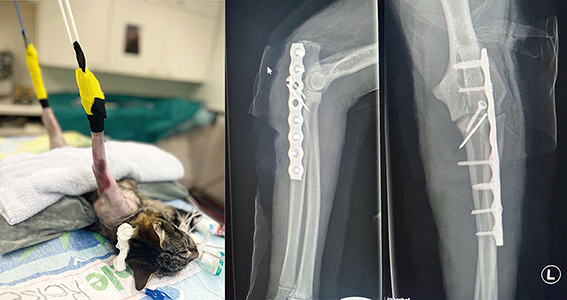

Beschwerden: komplizierte Femur- und Ellenbogenfraktur nach Unfall

Therapie: Chirurgische Versorgung beider Brüche

Tierklinik Lindenhof: «Kater «Mischu» wurde inzwischen erfolgreich operiert und wird zu Hause liebevoll von seinen neuen Besitzern gepflegt. Der quirlige Kater muss sich noch in Geduld üben, aber er macht sich in der Ruhebox ganz gut. In den nächsten Wochen werden noch einige Verbandwechsel anstehen, sowie eine Abschlussuntersuchung mit Röntgenkontrolle.»